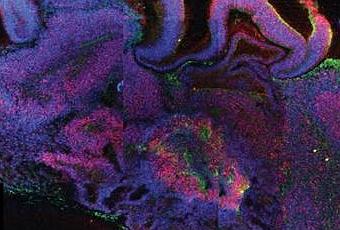

La complejidad del cerebro humano dificulta el estudio de los desordenes cerebrales en organismos modelo, lo que pone en evidencia la necesidad de un modelo in vitro del desarrollo del cerebro humano. Por este motivo, cientificos del Instituto de Biotecnologia Molecular de la Academia Austriaca de Ciencias, en Viena, han diseñado en el laboratorio un organoide tridimensional a partir de celulas iPS muy similar al cerebro humano durante las primeras etapas embrionarias. Para ello, el grupo austriaco recreo las condiciones de crecimiento que promovieron la diferenciacion de las celulas madre pluripotentes inducidas en diversos tejidos del cerebro humano embrionario. El resultado fue el desarrollo de diversas regiones cerebrales interdependientes como la corteza cerebral, la retina, las meninges y el plexo coroideo, que dieron lugar a un organoide del tamaño de un guisante con caracteristicas muy similares a las de un cerebro humano. Ademas, este pseudo-cerebro mostro un desarrollo similar al desarrollo cortical del cerebro humano, aunque el organoide solo sobrevivio 10 meses. Mas tarde, desarrollaron otro organoide a partir de celulas iPS de pacientes con microcefalia[i], un desorden que ha sido dificil de estudiar en ratones por la mayor complejidad del cerebro humano con respecto a los del resto de animales. De esta manera, obtuvieron un organoide cerebral afectado por este trastorno que les condujo a la hipotesis de que la diferenciacion neuronal en personas con microcefalia ocurre antes de tiempo durante el desarrollo embrionario, de manera que las celulas madre y progenitoras no contribuyen al crecimiento del cerebro de la misma manera que lo harian en un cerebro sano. Los autores concluyen que este trabajo demuestra la diferenciacion neuronal prematura en los organoides cerebrales derivados de pacientes que sufren microcefalia, lo que podria ayudar a explicar el fenotipo de la enfermedad. En conjunto, los resultados de esta investigacion desvelan el potencial de los organoides cerebrales tridimensionales como modelos del desarrollo del cerebro humano y como modelos de los trastornos cerebrales. Por tanto, este estudio supone un gran avance en la investigacion del cerebro humano en la medida en que abre la puerta al desarrollo de modelos del cerebro humano que permitiran estudiar en profundidad los trastornos cerebrales y analizar los efectos de los productos quimicos en el cerebro para desarrollar terapias contra defectos cerebrales y trastornos neuronales. Mas informacion: Nature